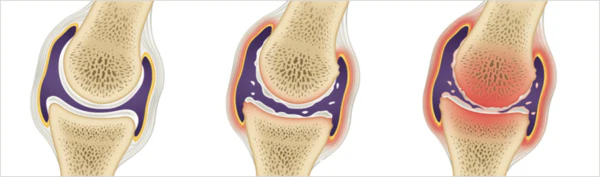

통풍이란 요산이 체내에 쌓여 관절에 염증을 일으키는 질병으로, 관절이 혹처럼 튀어나와 보일 정도로 심한 증상을 유발한다. 통풍이라 불리는 이 질병은 고통스럽고 찌르는 통증을 동반하며, 바람이 불면 더욱 심해지는 것이 특징이다. 이러한 고통은 주로 밤이나 새벽에 나타나며, 급성인 경우 일주일에서 한 달 동안 지속될 수 있다. 만성적인 경우에는 요산배설촉진제를 사용하여 치료된다.

통풍은 주로 체내에 과다 축적된 요산으로 인해 발생합니다. 요산은 우리가 섭취하는 다양한 음식이 소화되어 최종적으로 대사된 후 혈액에 녹아 있다가 소변으로 배출되는 물질입니다. 일반적으로 혈액 내에서 요산은 정상 수준을 유지하며 배설됩니다. 그러나 통풍 환자는 혈액 내 요산이 과다하게 증가합니다. 이러한 과다 축적된 요산은 결정체로 변화하고, 이러한 결정체가 관절 내에 침착하여 염증을 일으킵니다.

통풍을 적절히 치료하지 않을 경우, 발작성 관절염의 빈도가 증가하고 침범하는 관절 수도 더 많아지며, 회복에 필요한 시간도 증가합니다. 반복적인 관절염은 관절을 점차 손상시키며, 만성적인 관절염으로 진행될 수 있습니다. 또한 통풍성 결절이라 불리는 덩어리가 관절 주위나 피부 조직에 나타날 수 있습니다. 이러한 결절은 요산 결정체의 덩어리로 어느 부분에서든 형성될 수 있으며, 주로 팔꿈치, 귀, 손가락, 발가락, 발목 등에서 발생할 수 있습니다. 때로는 요로 결석을 형성하기도 합니다.